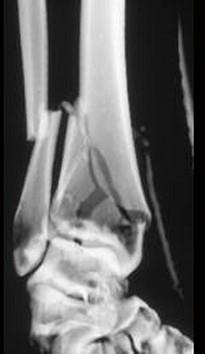

问题 男,45岁,车祸后10小时,请结合影像学检查,选出最可能的诊断 ( )

选项 A、柯莱斯骨折 B、加莱阿齐骨折 C、尺桡骨骨折 D、蒙泰贾骨折 E、胫腓骨骨折

答案 E